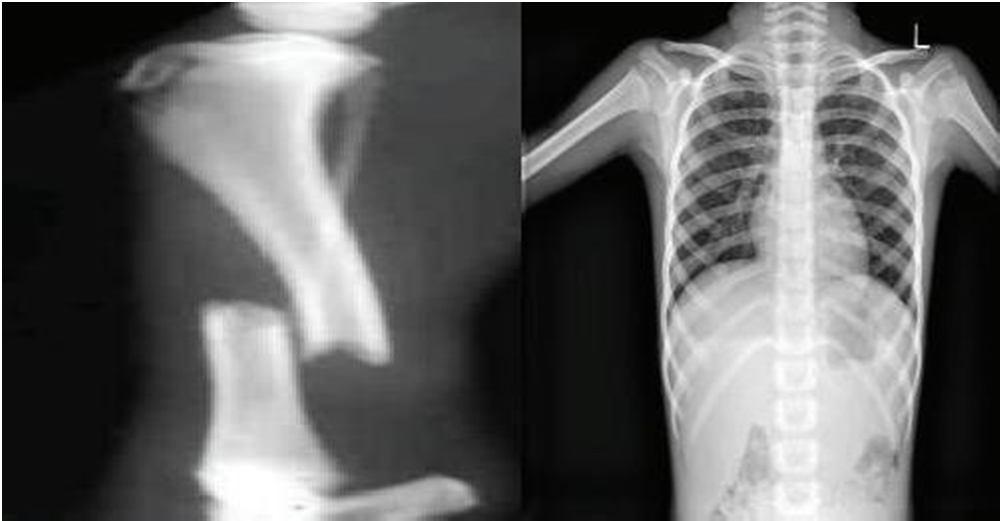

This part comprises information assortment, the evolution of information utilizing differences in the picture, and the characterization of sound and malignant bone utilizing profound CNN. The analysis has been executed on the bone X ray picture informational collections, assembled from various sources accessible for analysis, for example, the Cancer Imaging Archive(TCIA) and the Indian Institute of Engineering Science and Technology.

Fig 3: X Ray Image

The pictures of the interludes are restrained in the preliminary stage, involving different picture handling methods to determine the status. Likewise, the variety stage follows, where a back engendering brain network trains the handled photographs before standing examined. The handling step and the collection approach are the two critical periods of the suggested framework. During the picture handling stage, methods like Haar Wavelet changes and SIFT as a feature extractor are operated to trade with the images. These techniques further develop the pictures' quality and eliminate the bone's cracked region. The photos are ready to be accepted care of in the brainiac network at the end of this step.